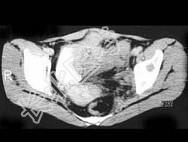

- 单项选择题女,54岁, 因反复左髋、左下肢痛伴左下肢活动障碍约半年,结合所提供的图像, 最可能的诊断是 ( )

A、骨髓瘤

B、滑膜肉瘤

C、骨转移瘤

D、尤文肉瘤

E、骨巨细胞瘤